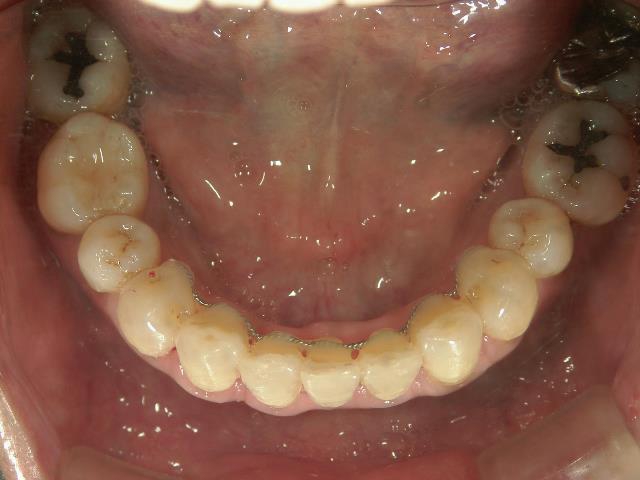

矯正歯科 治療前矯正歯科 治療前

矯正歯科 治療前

矯正_灰色.pngno.12_5333_治療前_下.jpg矯正_灰色.png